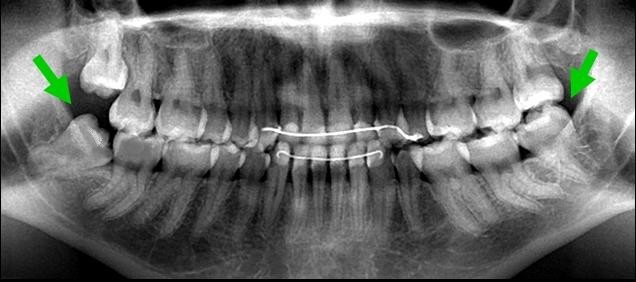

Зубы мудрости на рентгеновском снимке

На следующем этапе нужно сделать ортопантомограмму. Панорамный рентгеновский снимок дает максимально четкую картинку, на которой видно, как располагаются восьмерки по отношению к остальным зубам. Снимок позволяет более точно определиться со схемой лечения.

где находится и как выглядит зуб мудрости на ОПТГ